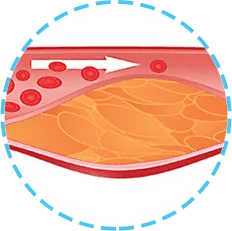

El aumento del nivel de colesterol en la sangre puede indicar la formación de placas en los vasos.

Las placas se asientan en las paredes de los vasos y no permiten la circulación sanguínea o la obstruyen completamente.

La hipertensión no solo es la elevación de la presión que puede bajarse tomando una capsula. Es un estado en el cual los vasos sanguíneos se estiran y se adelgazan y en sus paredes aparecen sedimentos de colesterol. Como resultado, esto conduce a una interrupción del flujo sanguíneo y al mal funcionamiento de uno u otro órgano.